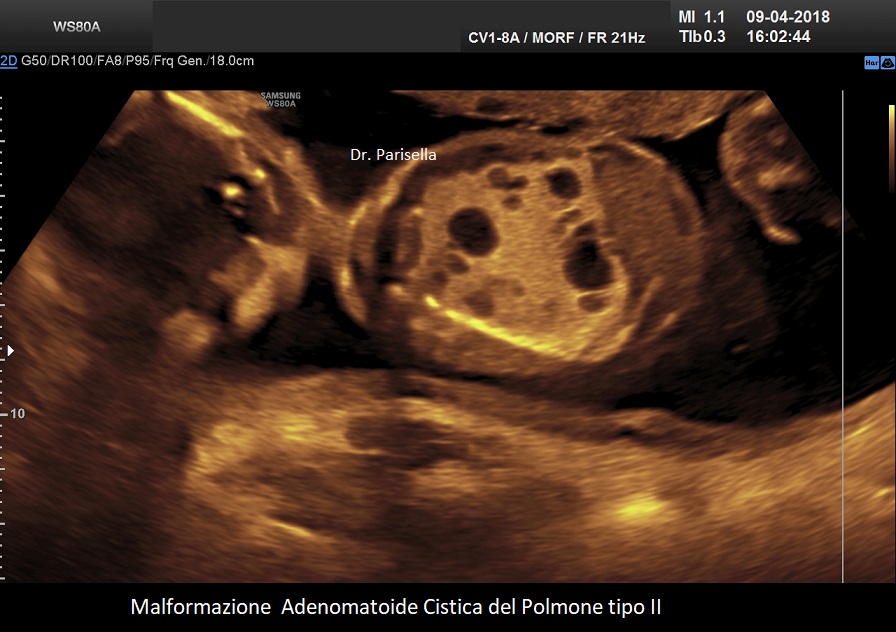

MACP tipo II: è caratterizzato da numerose piccole cisti di diametro < 2,0 cm.;

. Le lesioni di tipo II si verificano in circa il 40% dei casi e sono costituite da numerose piccole cisti (< 2,0 cm) mescolate con aree di aumentata ecogenicità all'ecografia. La prognosi dipende dalla gravità della lesione e dalla sua associazione con altre malformazioni fetali. Esiste una associazione tra anomalie congenite e CCAM di tipo II, le principali delle quali sono genitourinarie, come la disgenesia o l'agenesia renale, e cardiache, come la tetralogia di Fallot e il tronco arterioso; altri includono l'ernia diaframmatica e le anomalie muscoloscheletriche. Un importante studio, considerato una delle più grandi coorti di casi, conclude che le CCAM microcistiche e macrocistiche presentano entrambe decorsi e prognosi perinatali simili (Chen Y et al., 2021).

Si presenta come una massa occupante spazio di solito unilaterale in più del 95% dei casi e solitamente coinvolge un lobo o segmento del polmone; nella sua evoluzione determina dislocazione del mediastino e del cuore. L'ecostruttura distingue due forme: una forma multicistica  caratterizzata dalla presenza di multiple cisti di varia grandezza (tipo I e II) e una forma microcistica (tipo III) corrispondente alla variante solida.